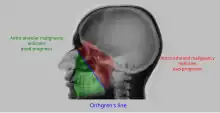

| Maxillary sinusitis[2] | ![]() Differentiating pathology in maxillary sinus

| Malignancy |

![]() Onhgren's line